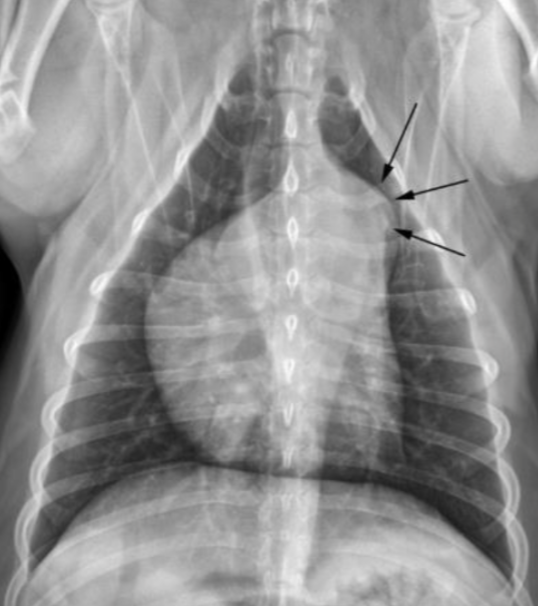

| Generalized cardiomegaly |

|---|

| RA, RV, LA, LV๊ฐ ๋ค ์ปค์ง โ Globoid heart |

| - Pericardial effusion - ์ฌํ ์์ชฝ ์ฌ์ฅ๋ณ (MVI + TVI) - PPDH (Peritoneopericardial diaphragmatic hernia) - Cardiomyopathy (DCM) - Anesthesia, bradycardia |

![]() |